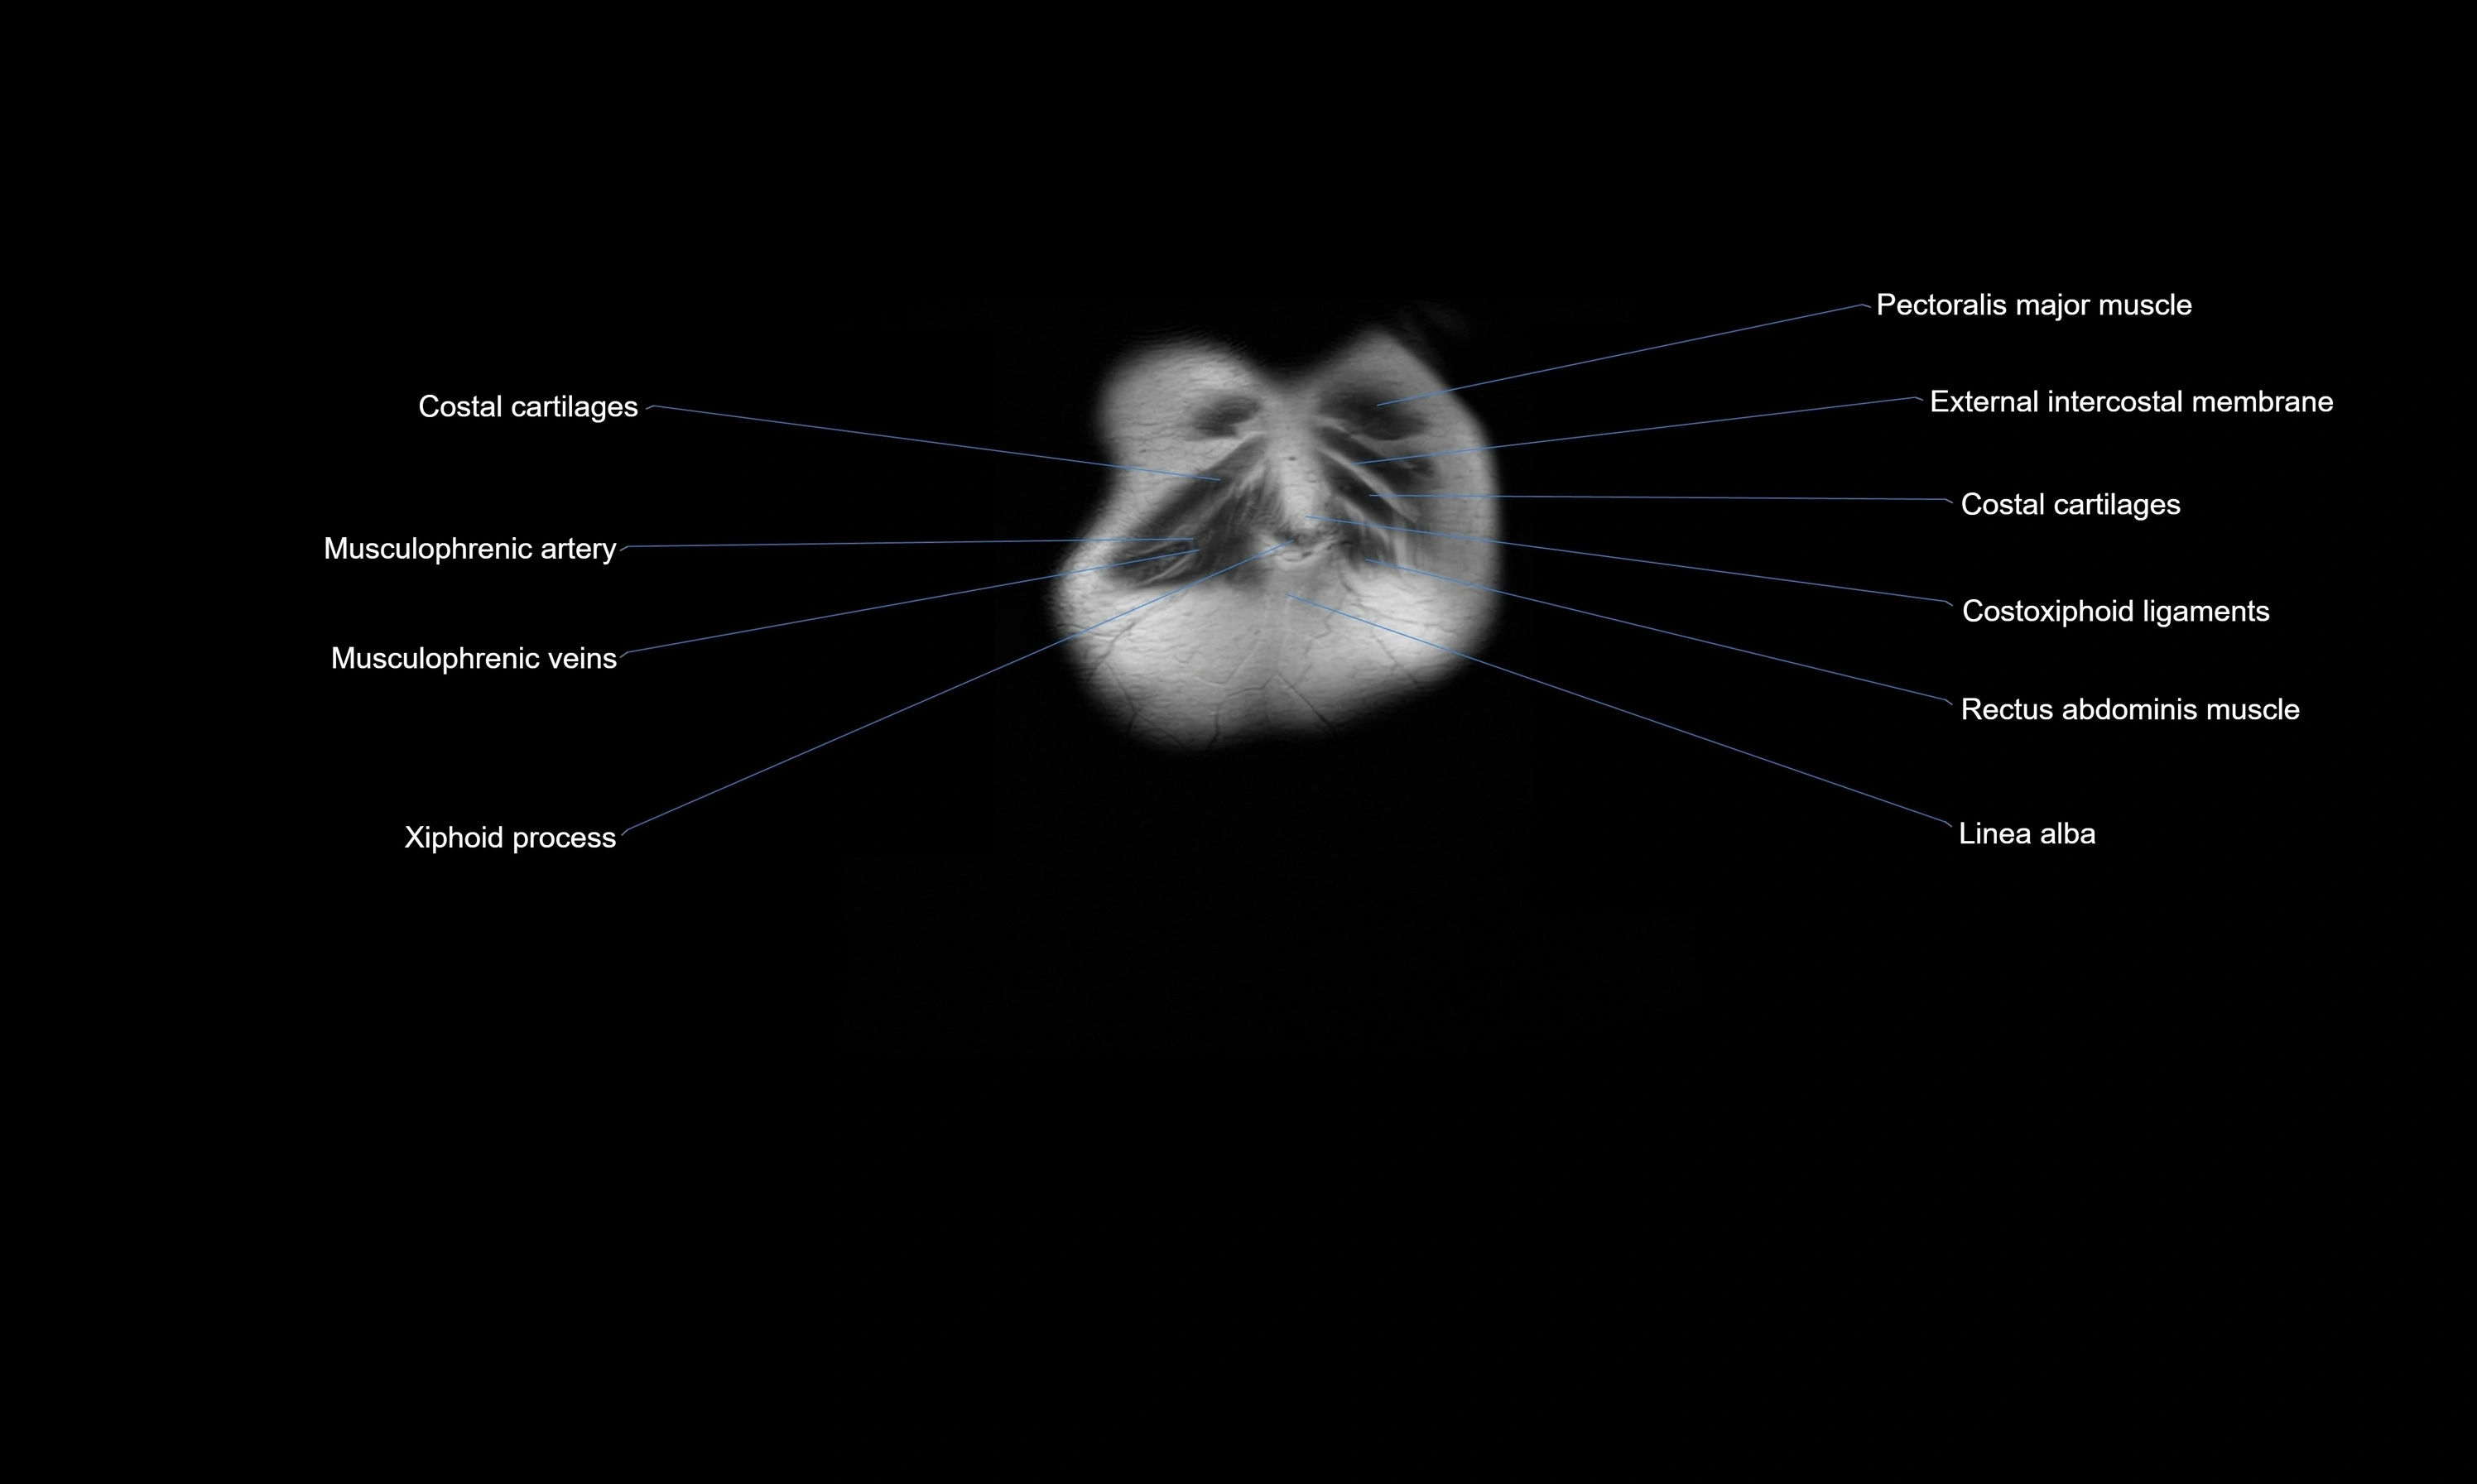

MRI images